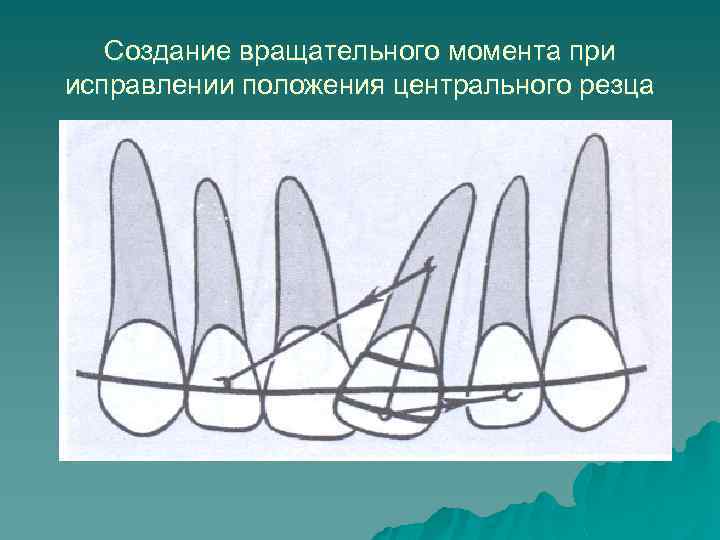

Создание вращательного момента при исправлении положения центрального резца

При лечении асимметричной диастемы, которая возникает при латеральном смещении одного центрального резца, следует воздействовать только на этот зуб. Выбор ортодонтической техники зависит от положения центрального резца, которое может быть различным: параллельное со смещением от средней линии, когда корень и коронка зуба смещены на одинаковое расстояние от средней линии; коронка зуба смещена более значительно, чем его корень; корень зуба - более значительно, чем его коронка